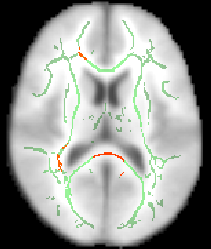

All of the above (apart from setting the skeleton transparency, which has to be done by hand in the GUI) can be carried out with a single command (see first example image):

fsleyes $FSLDIR/data/standard/MNI152_T1_1mm mean_FA_skeleton -cm green -dr 0.2 0.7 tbss_tfce_corrp_tstat1 -cm red-yellow -dr 0.95 1